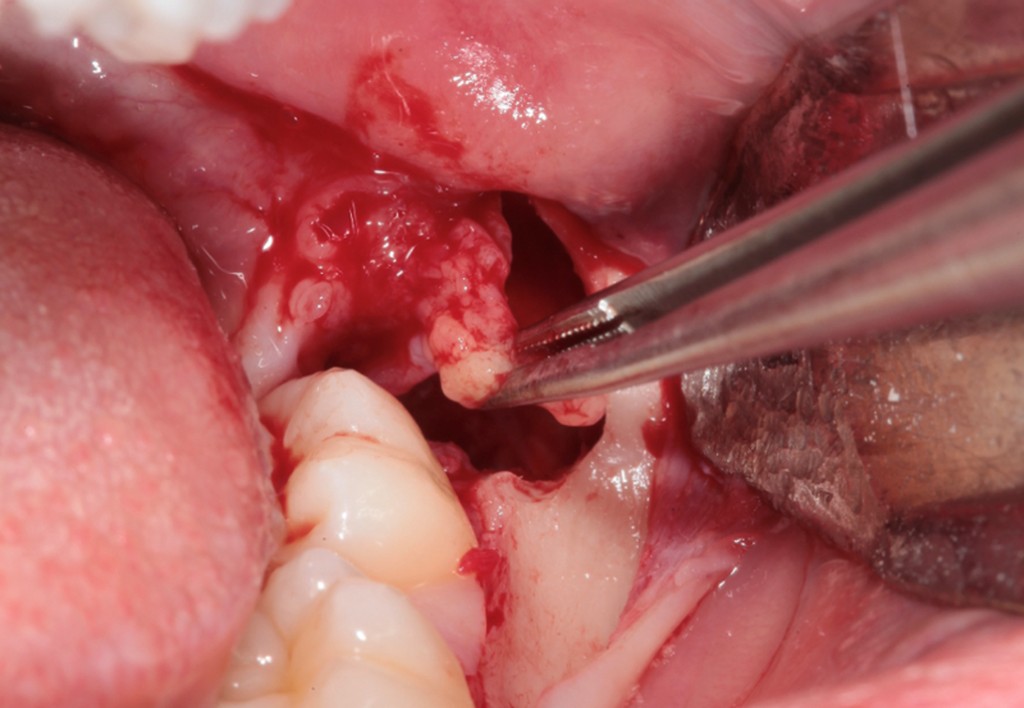

► Socket preservation

Strategie per mantenere il volume della cresta ossea e dei tessuti molli, con focus su biomateriali e tempi di guarigione.

Galleria fotografica